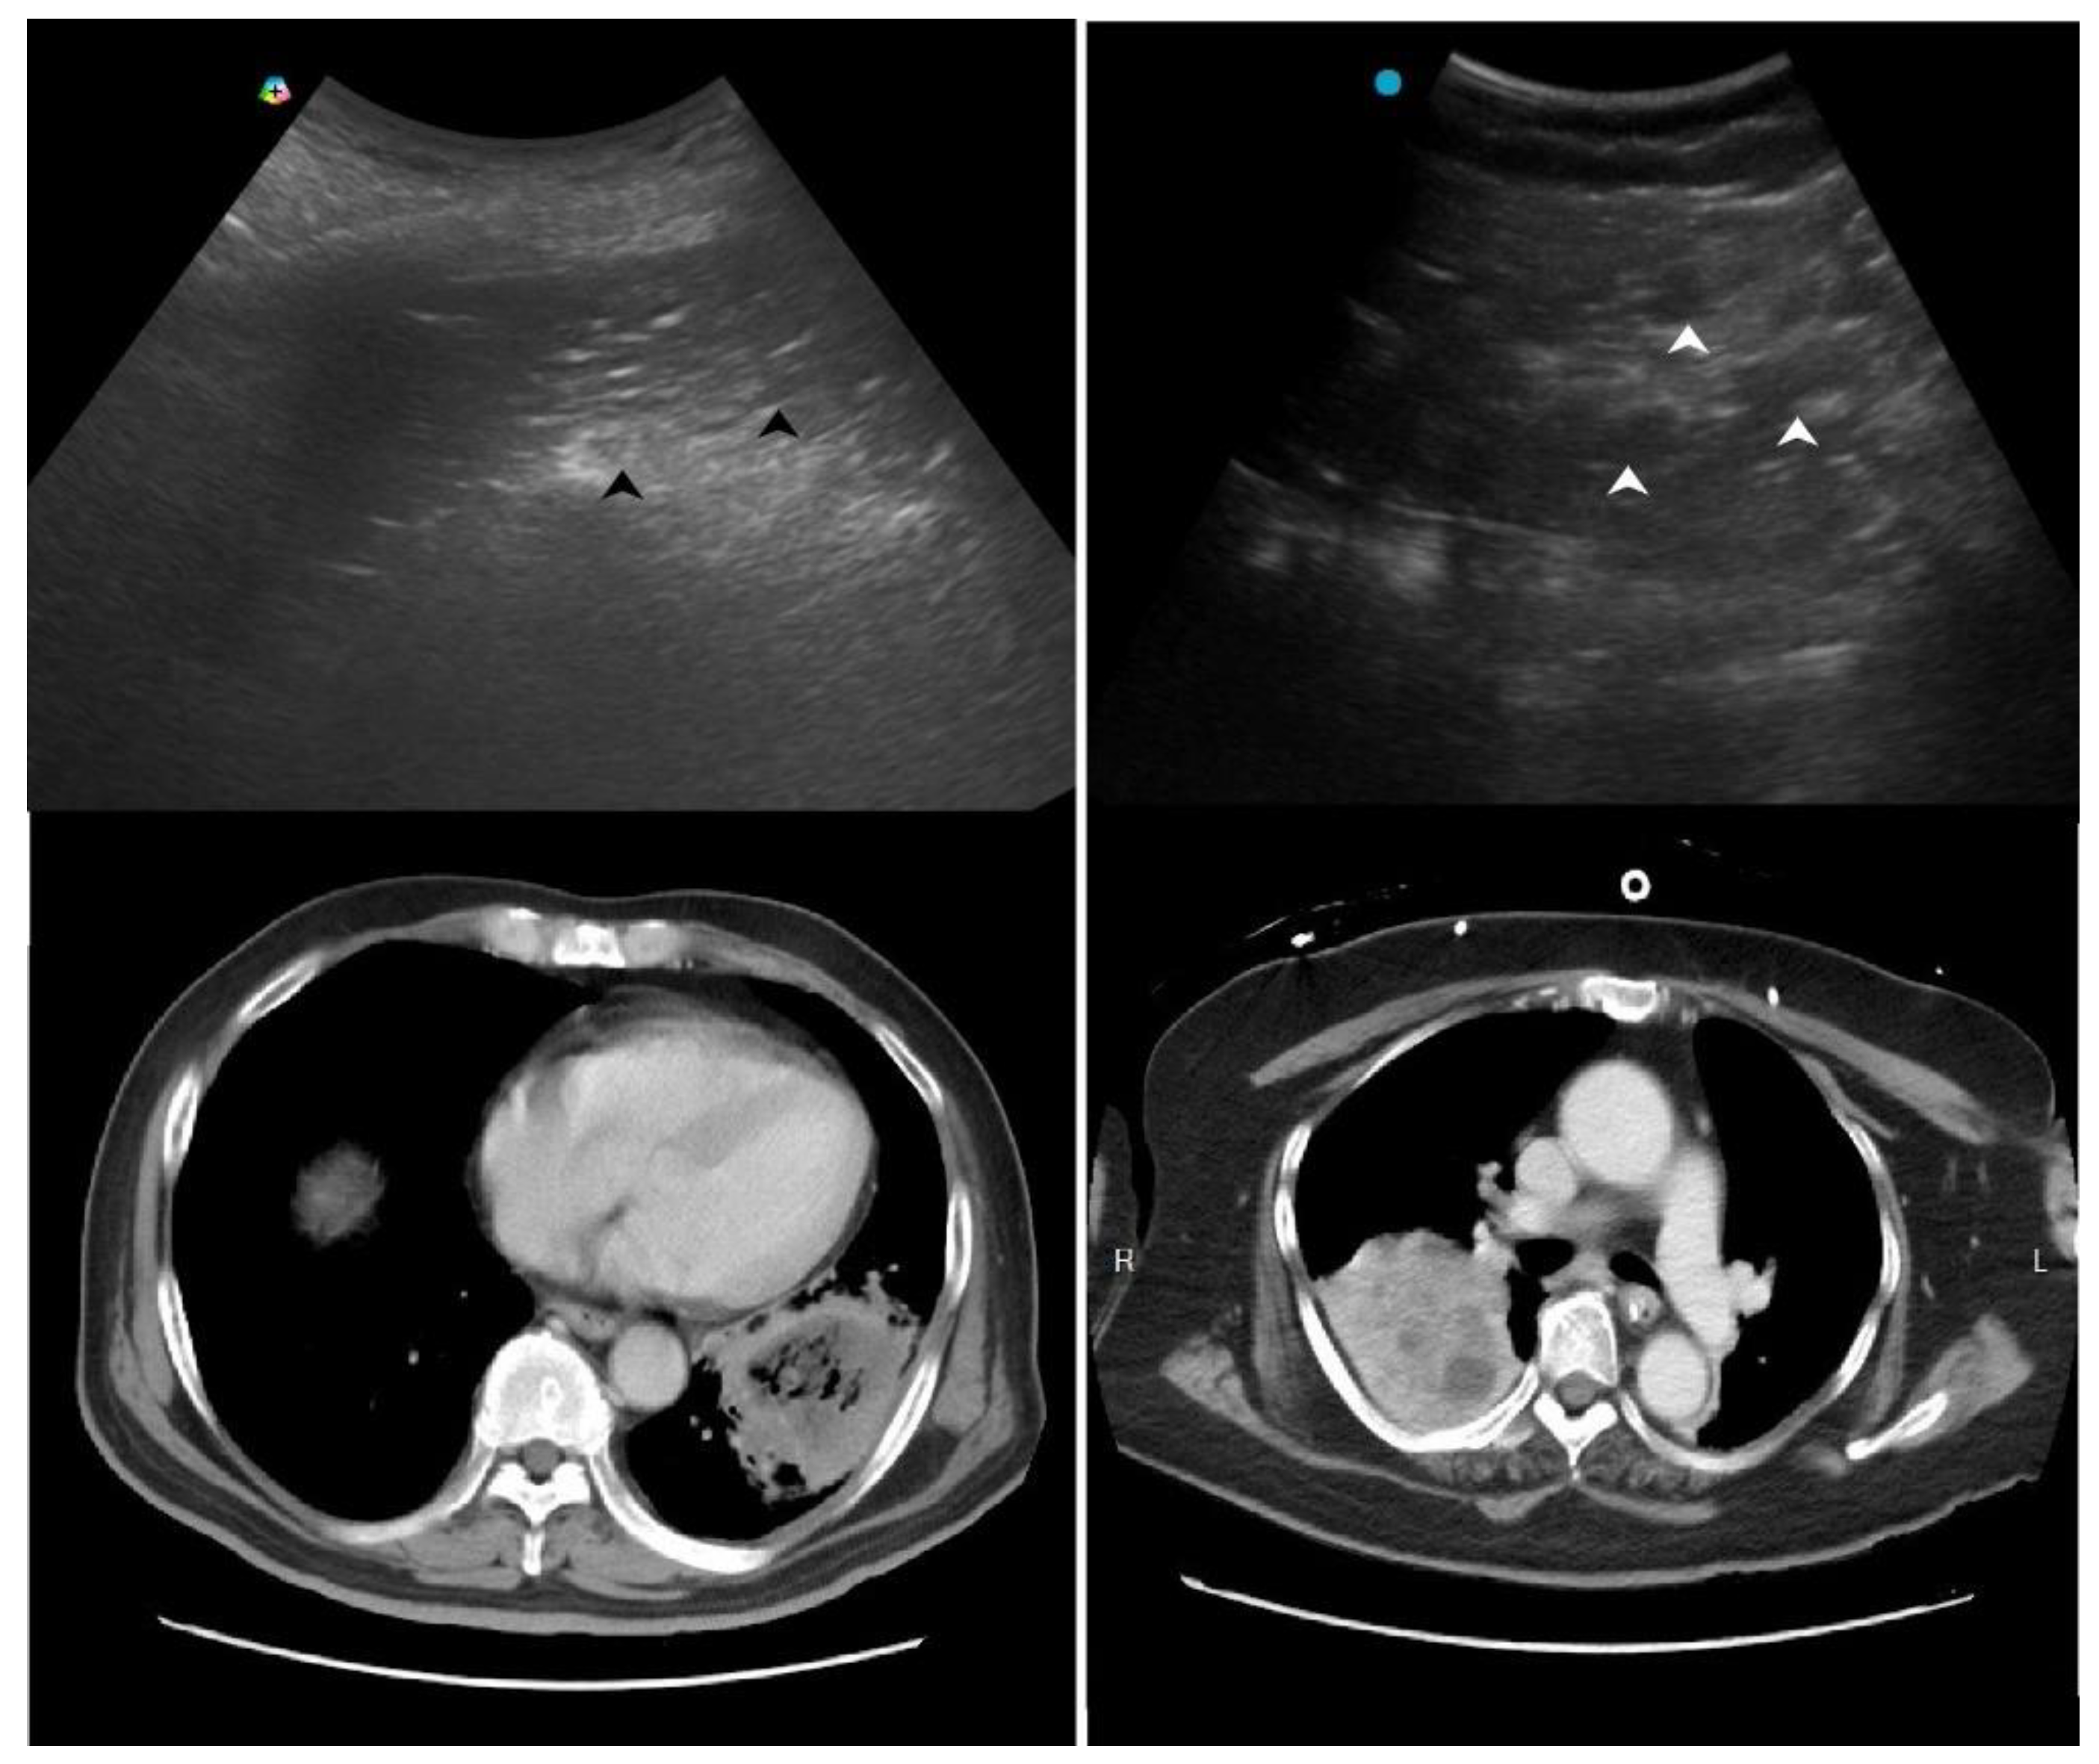

2.1. Red Flag Signs Related to ARDS

Several LUS signs, based on previous studies, indicate a more severe pneumonia, such as acute lung injury or acute respiratory distress syndrome (ARDS). A landmark study sough to differentiate acute pulmonary edema (APE) from ARDS by LUS. Although B-lines (alveolar-interstitial syndrome) prevailed 100% in both APE and ARDS, absence or reduction of the pleural gliding (sliding) was observed in 100% of patients with ARDS and in 0% of patients with APE. ‘Spared areas’ within confluent B-lines were observed in 100% of patients with ARDS and in 0% of patients with APE [21]. In addition, pleural line abnormalities, including irregularity or thickening, were observed in 100% of patients with ALI/ARDS (Figure 1). These signs are classified as level B of evidence with strong recommendation in a landmark LUS guideline [22].

Figure 1. Pleural irregularity and thickening (arrows) in a patient with acute respiratory distress syndrome.